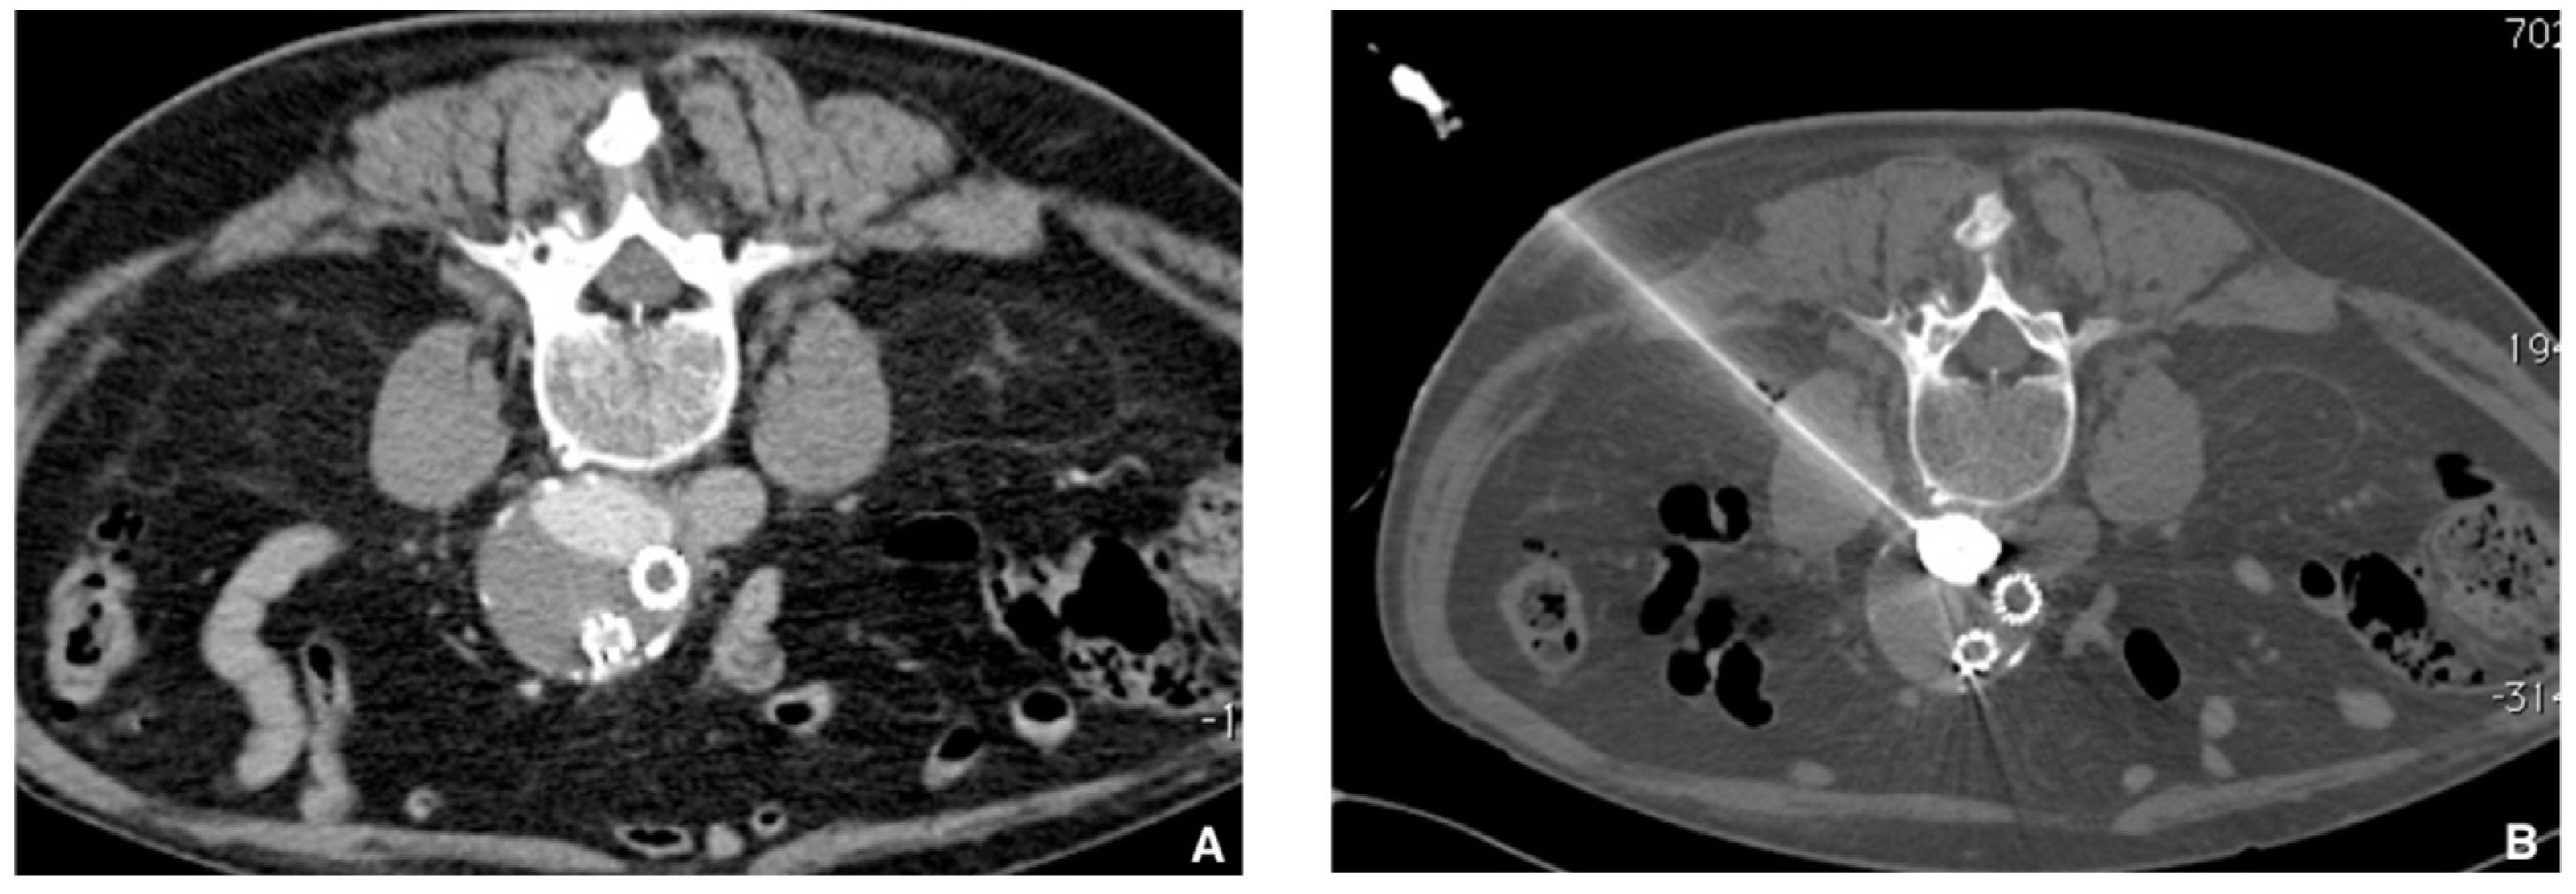

Figure 9. Type 2 endoleak from lumbar ateries. (A) Computer tomography (CT) scan with contrast injection in procubitus position showing posterior opacification of the periprothetic aneusrysmal sac (nidus). (B) Translumbar puncture of the nidus of the endoleak under CT guidance with a metallic needle. Insertion of a microcatheter inside and embolization of the nidus with a Glubran®2/lipiodol mixture (1:4 ratio) until complete nidus opacification.